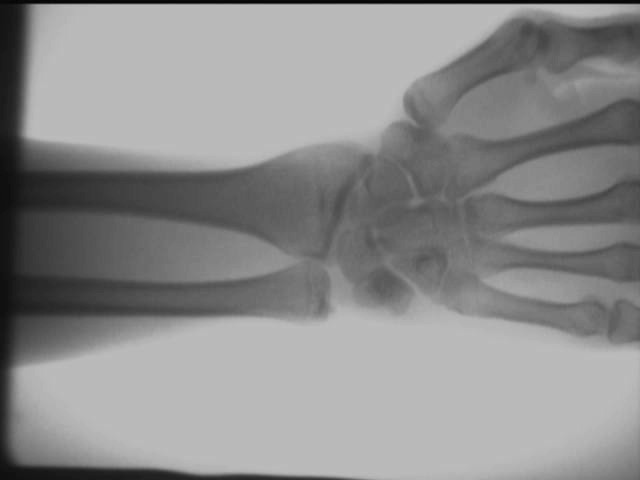

تأثير مفصل كاحل اليد

يتم الحصول على نتائج الاختبار المذكورة أعلاه في الموقع باستخدام AS-C200جهاز الأشعة السينية المحمول